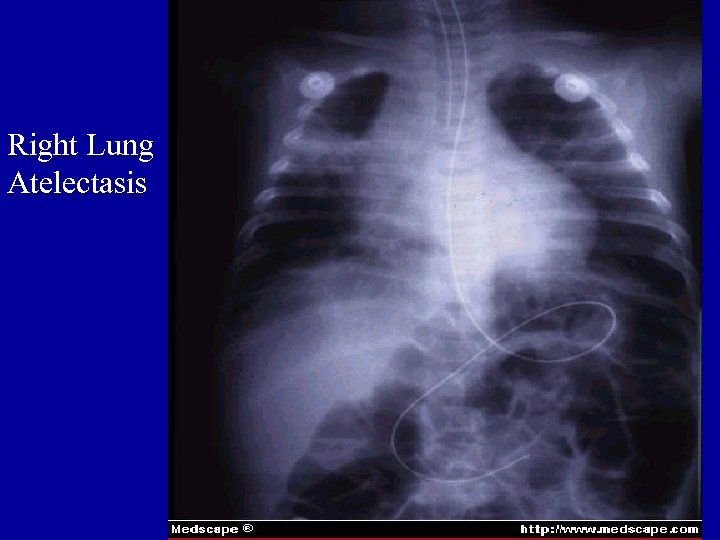

Right Lung Atelectasis